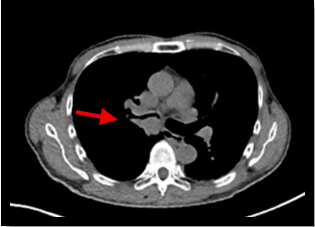

肺がん原発巣の症例。(病変部は赤矢印)

CT画像→病変部がわかりにくい

PET画像 → 解剖部位がわかりにくい

PET画像とCT画像を重ね合わせることで、病変が存在する解剖部位が分かるため診断能が高くなる